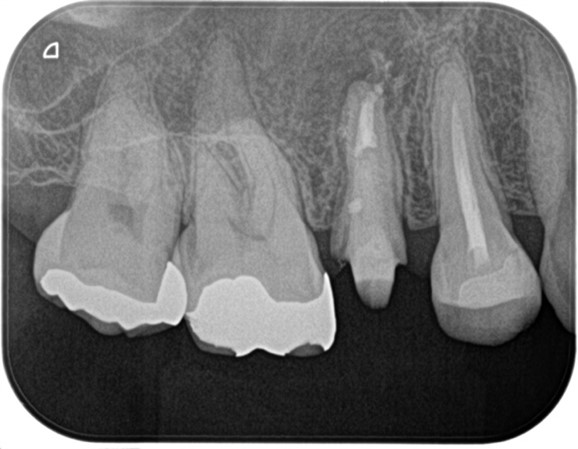

精密根管治療終了後、3ヶ月間仮歯で症状の経過を確認し、予後良好と判断して最終補綴物へ移行しました。

経過2年の段階で根尖に確認できた根尖性歯周炎は縮小し、予後良好の経緯を確認しています。